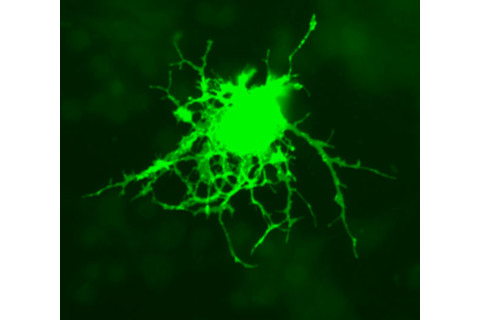

一种叫做少突胶质细胞的细胞,能制造髓磷脂。

图片由Methoxyroxy / Wikimedia Commons 提供